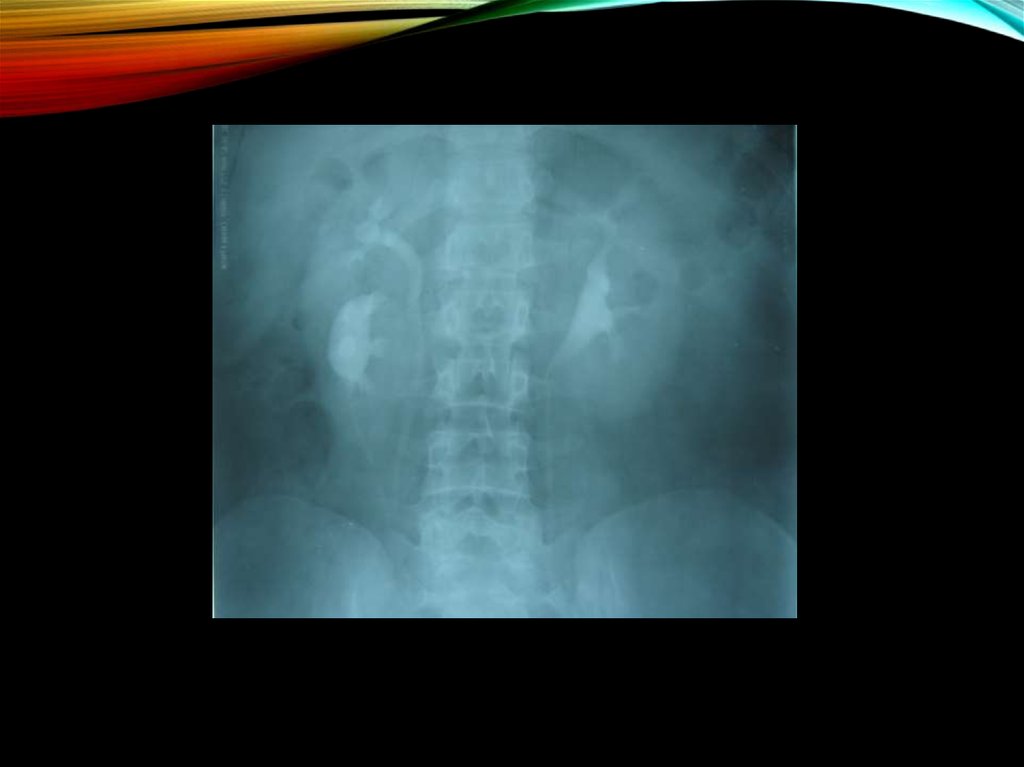

19. Изменения рентгенологической картины:

ИЗМЕНЕНИЯ РЕНТГЕНОЛОГИЧЕСКОЙ

КАРТИНЫ:

экскреторная урография

снижение тонуса верхних мочевых путей

уплощенность и закругленность углов форниксов

сужение и вытянутость чашечек

позднее - деформация чашечек, сближение их

пиелоренальные рефлюксы

пиелоэктазии

асимметрия размеров почек

ретроградная пиелография:

картина гипоплазированной почки;

почечная ангиография (в редких случаях):

уменьшается просвет почечной артерии

периферическое кровоснабжение обедняется

облитерируются мелкие сосуды коркового

вещества.